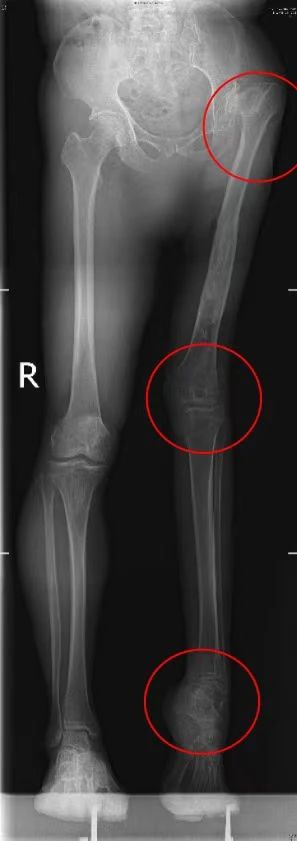

因其左下肢三大关节(髋、膝、踝)均出现畸形,不等长,大大增加了手术难度。得益于我院在微创关节置换的先进技术和丰富经验,徐杰教授带领团体周密术前设计,成功为王大伯行微创髋关节置换术,术后第三天他便可拄拐下地行走。

术前左下肢三大关节(髋、膝、踝)全部畸形